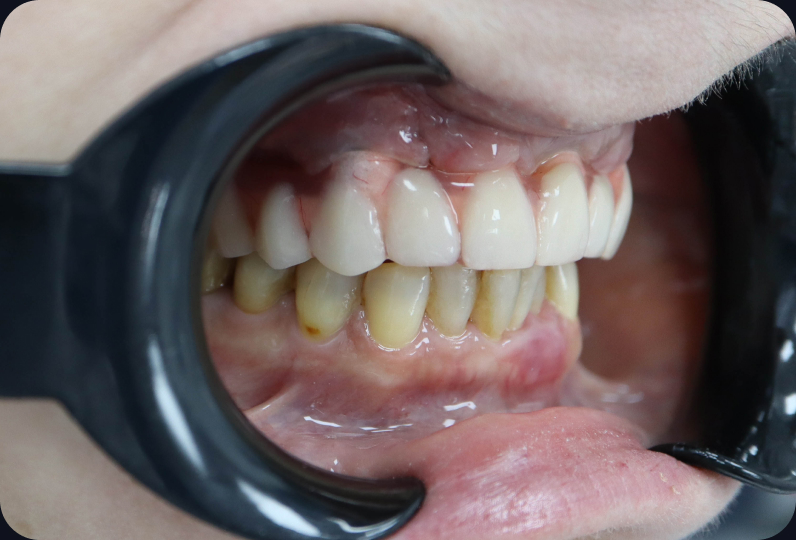

результаты

Установлен условно-съемый металлоакриловый протез на 12 зубов

Вид протеза сбоку